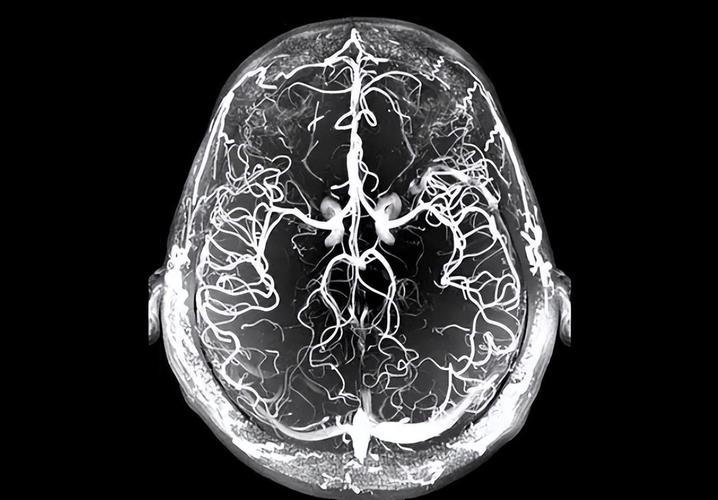

第一部分:什么是TCD检查?

TCD 的全称是 经颅多普勒超声 (Transcranial Doppler Ultrasound)。

这是一种无创、无痛的检查方法,医生会在您的头部特定位置(如太阳穴、眼眶、后颈等)放置一个超声波探头,就像做B超一样,这个探头能穿透颅骨的薄弱区域,直接“听到”和“看到”大脑内部主要血管(如大脑中动脉、大脑前动脉、基底动脉等)的血流情况。